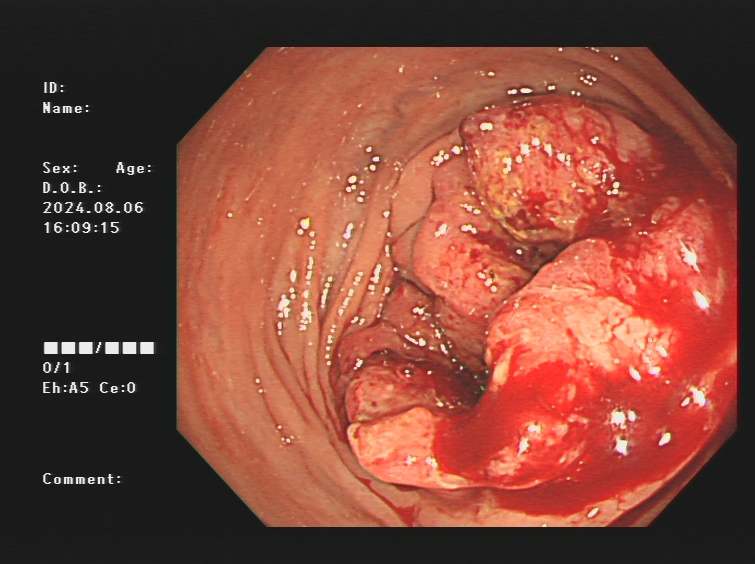

1.上消化道出血常见原因:消化性溃疡(胃溃疡、十二指肠溃疡)、食管炎、急性糜烂出血性胃炎、上消化道肿瘤(食管癌、胃癌)、剧烈呕吐造成的食管贲门黏膜撕裂伤、肝硬化引起的食管胃底静脉曲张。以下是一些常见的上消化道出血内镜图片:

食管癌、胃癌出血